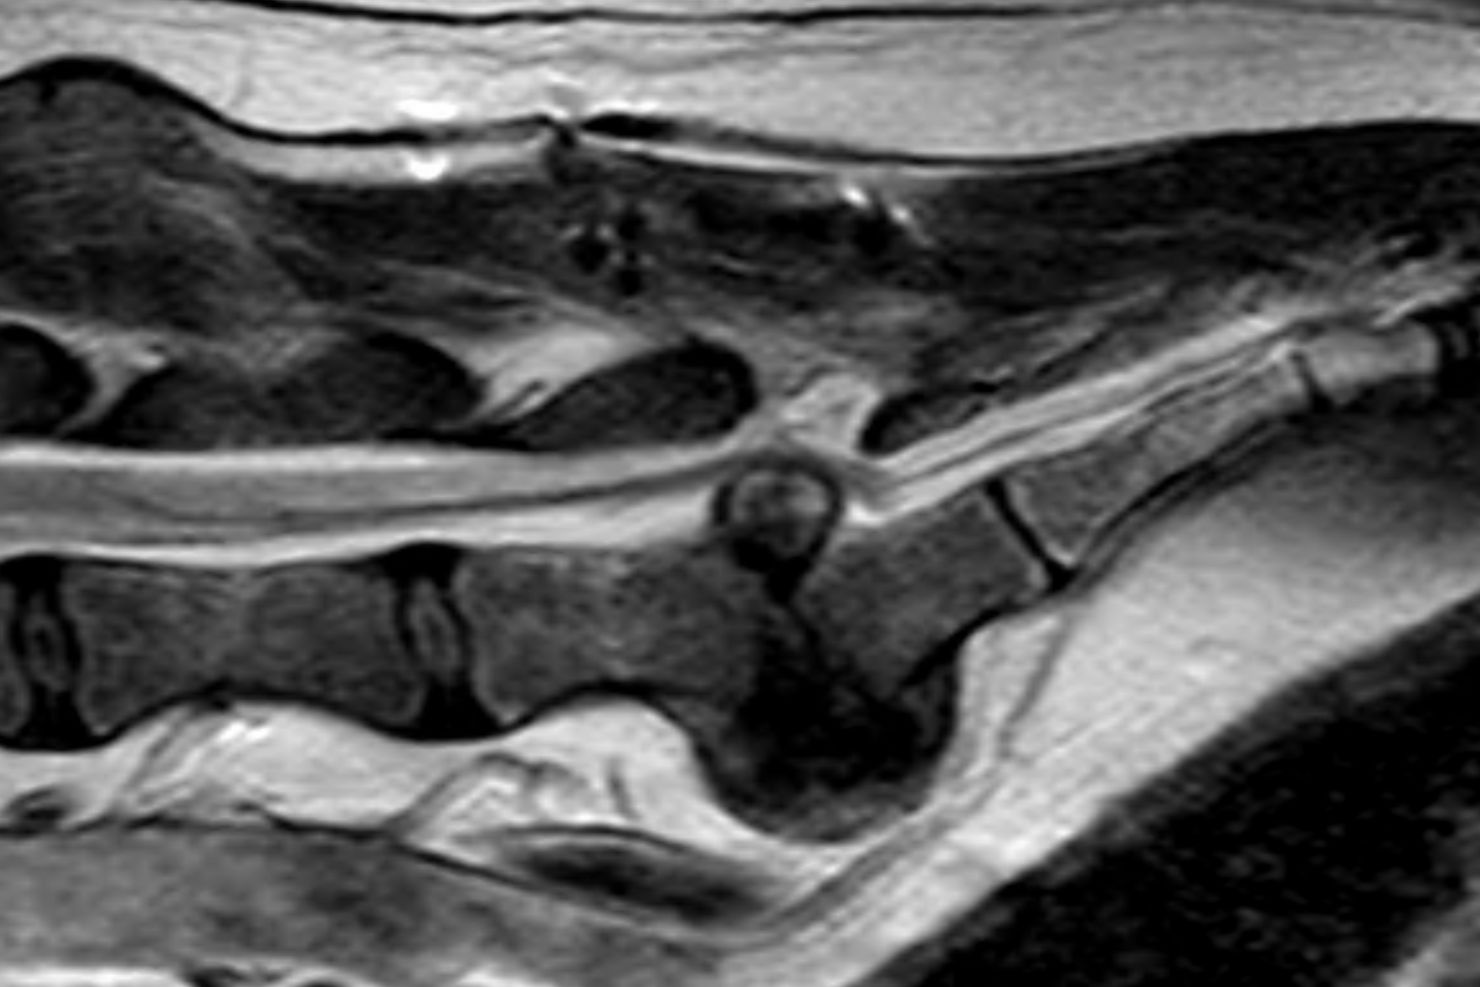

Zentral ist für mich lumbosakraler Druckschmerz bei Palpation in Kombination mit dem Vorstellungsgrund „Möchte nicht mehr springen / Stiegen steigen / ballspielen“ oder einer leichten Lahmheit. Wichtig ist es, sowohl eine neurologische als auch eine orthopädische Untersuchung durchzuführen, da die Symptome eben nicht charakteristisch für eine neurologische Erkrankung sind. Der Ausschluss von orthopädischen Problemen ist sehr wichtig – da ältere Patienten betroffen sind, kann es sein, dass beide Probleme vorliegen. Das erschwert die Diagnosestellung und man braucht weitere Schritte zur Bestätigung. Röntgenbilder können die Verdachtsdiagnose erhärten, aber nicht bestätigen. Um sie zu bestätigen, braucht man schnittbildgebende Verfahren wie etwa CT oder MRT.